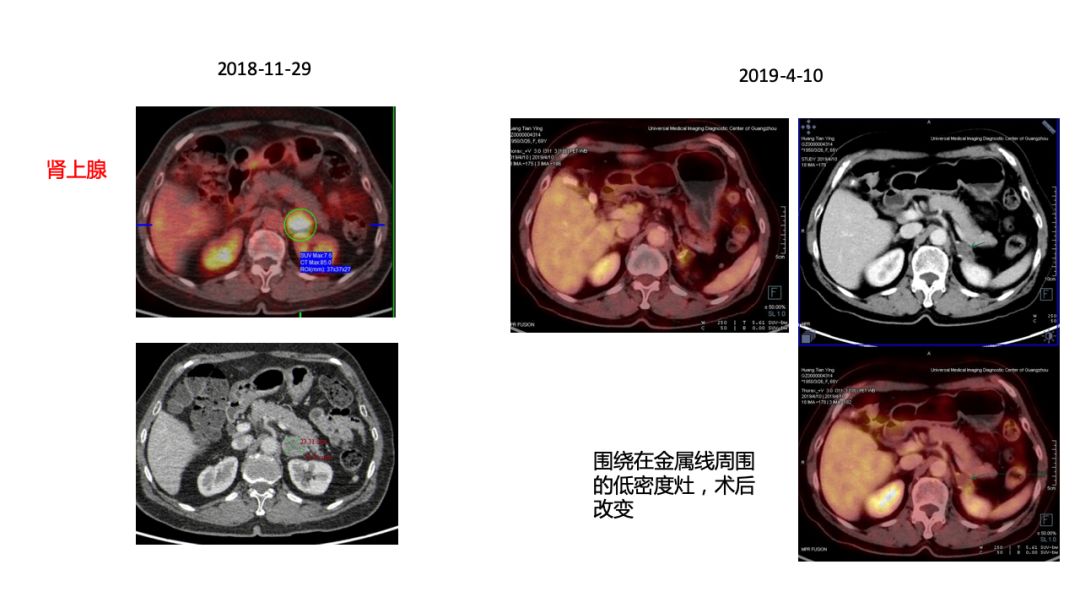

5)2018-12-07行肾上腺切除术,术后病理小细胞癌。

行基因检测EGFR、ALK等基因均为野生型,TMB 8mutw/Mb,MS Stable。